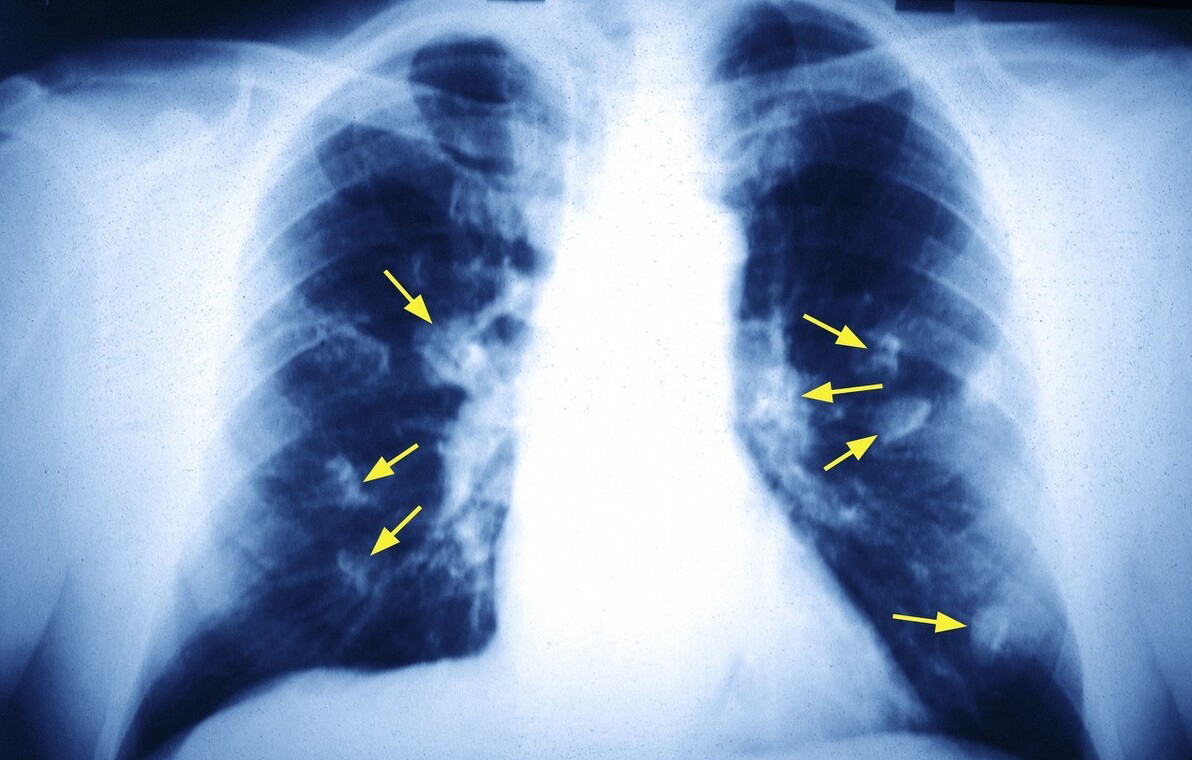

陈女士是我本科时的同学,在江苏某三甲医院做普外科医生,三年前,单位例行体检,她的左下肺有个8mm磨玻璃结节,右上肺有一个3mm的磨玻璃结节。左下肺结节伴有血管穿过,从大小、形态来看,都像恶性结节,于是进行了胸腔镜手术,病理提示肺原位腺癌。术后一直随访右上肺结节,有增大趋势。她调侃说,“我迟早要经历第二刀的”。像她这样,如果第二个结节确定也是肺癌,则属于多原发肺癌。

多原发肺癌(multiple primary lung cancer, MPLC)是指同一患者的肺内同时或先后发生两个或两个以上原发性肺癌。以诊断时间间隔6个月为界,分为同时性多原发肺癌和异时性多原发肺癌。同时确诊或先后确诊,间隔时间在6个月内的皆属于同时性多原发肺癌。先后确诊间隔时间超6个月的为异时性多原发肺癌。中国大约有3%的肺癌患者,会出现多原发的情况。

多原发肺癌发病原因目前比较公认的观点是“区域癌化”。意思是致癌因子长期作用于呼吸道上皮组织,引起细胞DNA损伤,经过长期的突变累积,最终发展为恶性肿瘤。致癌因子介导的DNA改变存在于整个呼吸道粘膜,支气管肺泡上皮可能发生广泛异型增生,其中某些高级别的异型增生细胞首先癌变,随着时间的推移,还可能有其他异型细胞相继癌变,形成多原发肺癌。在这一过程中,不同位置的组织细胞可能发生不同的基因突变,从而形成具有独立的不同克隆来源的多原发癌,而各个癌灶就表现出具有自身特异性的基因表型。

我的理解是,由于致癌因素和遗传基因的共同作用,呼吸道内的“土壤”不再健康,多个坏的“种子”同时或不同的时间,不同的地点“发芽”就形成了多原发肺癌。多原发肺癌可以是病理类型相同、基因型相同的癌。也可以是病理类型不同的癌,比如有的是腺癌,有的是鳞癌。也有可能都是腺癌,但基因型不同。